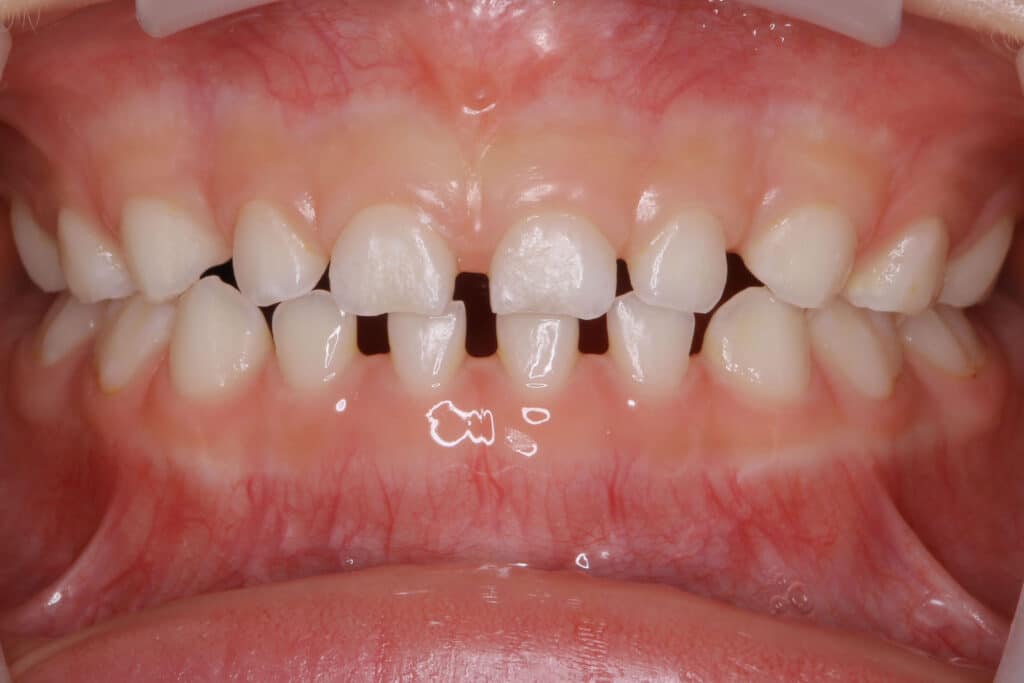

正中離開(すきっ歯)

「正中離開(せいちゅうりかい)」は前歯2本にすき間がある症状です。「すきっ歯」ともいいお子様によく見られます。

歯と歯の間にスキ間が空いている歯並びは「空隙歯列(くうげきしれつ)」といい、すき間が黒ずんで見える状態です。

▽正中離開(すきっ歯)になる原因

・永久歯の本数が少ない

・歯が小さい

・顎の成長が不十分

・舌で前歯を押すクセがある

・指しゃぶり、舌のクセ、爪咬みのクセ

すきっ歯の状態は、歯と歯の間に食べ物挟まりやすく、虫歯・歯周病の原因になります。歯の間から空気が漏れて、発音がしにくいです。